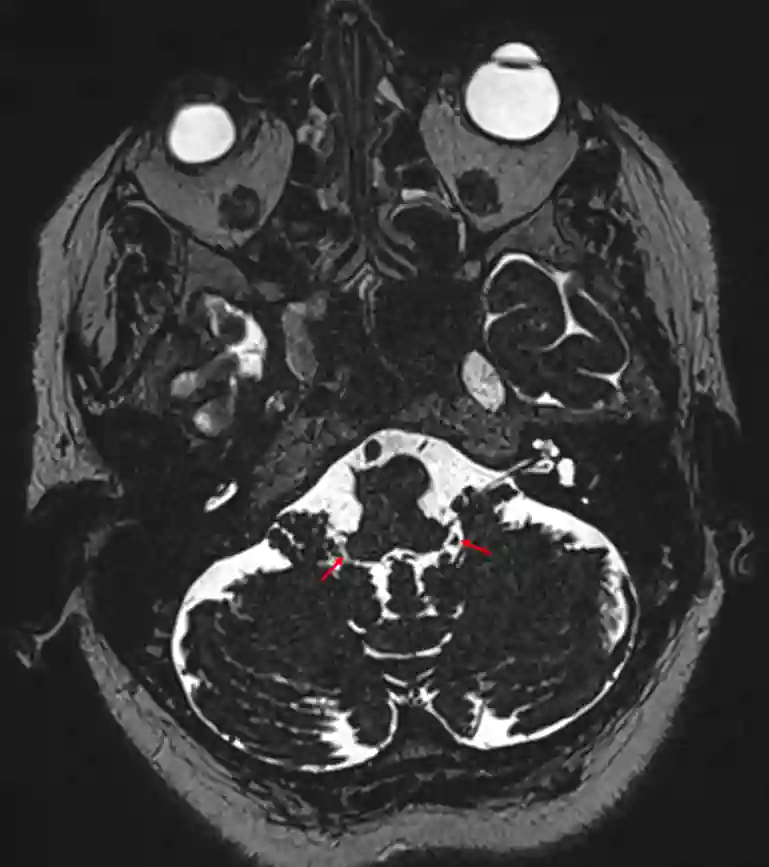

Foramen Luschkae im MRI

Markierung der Apertura lateralis ventriculi quarti (Foramen luschkae) in einer axialen MRI CISS Sequenz.